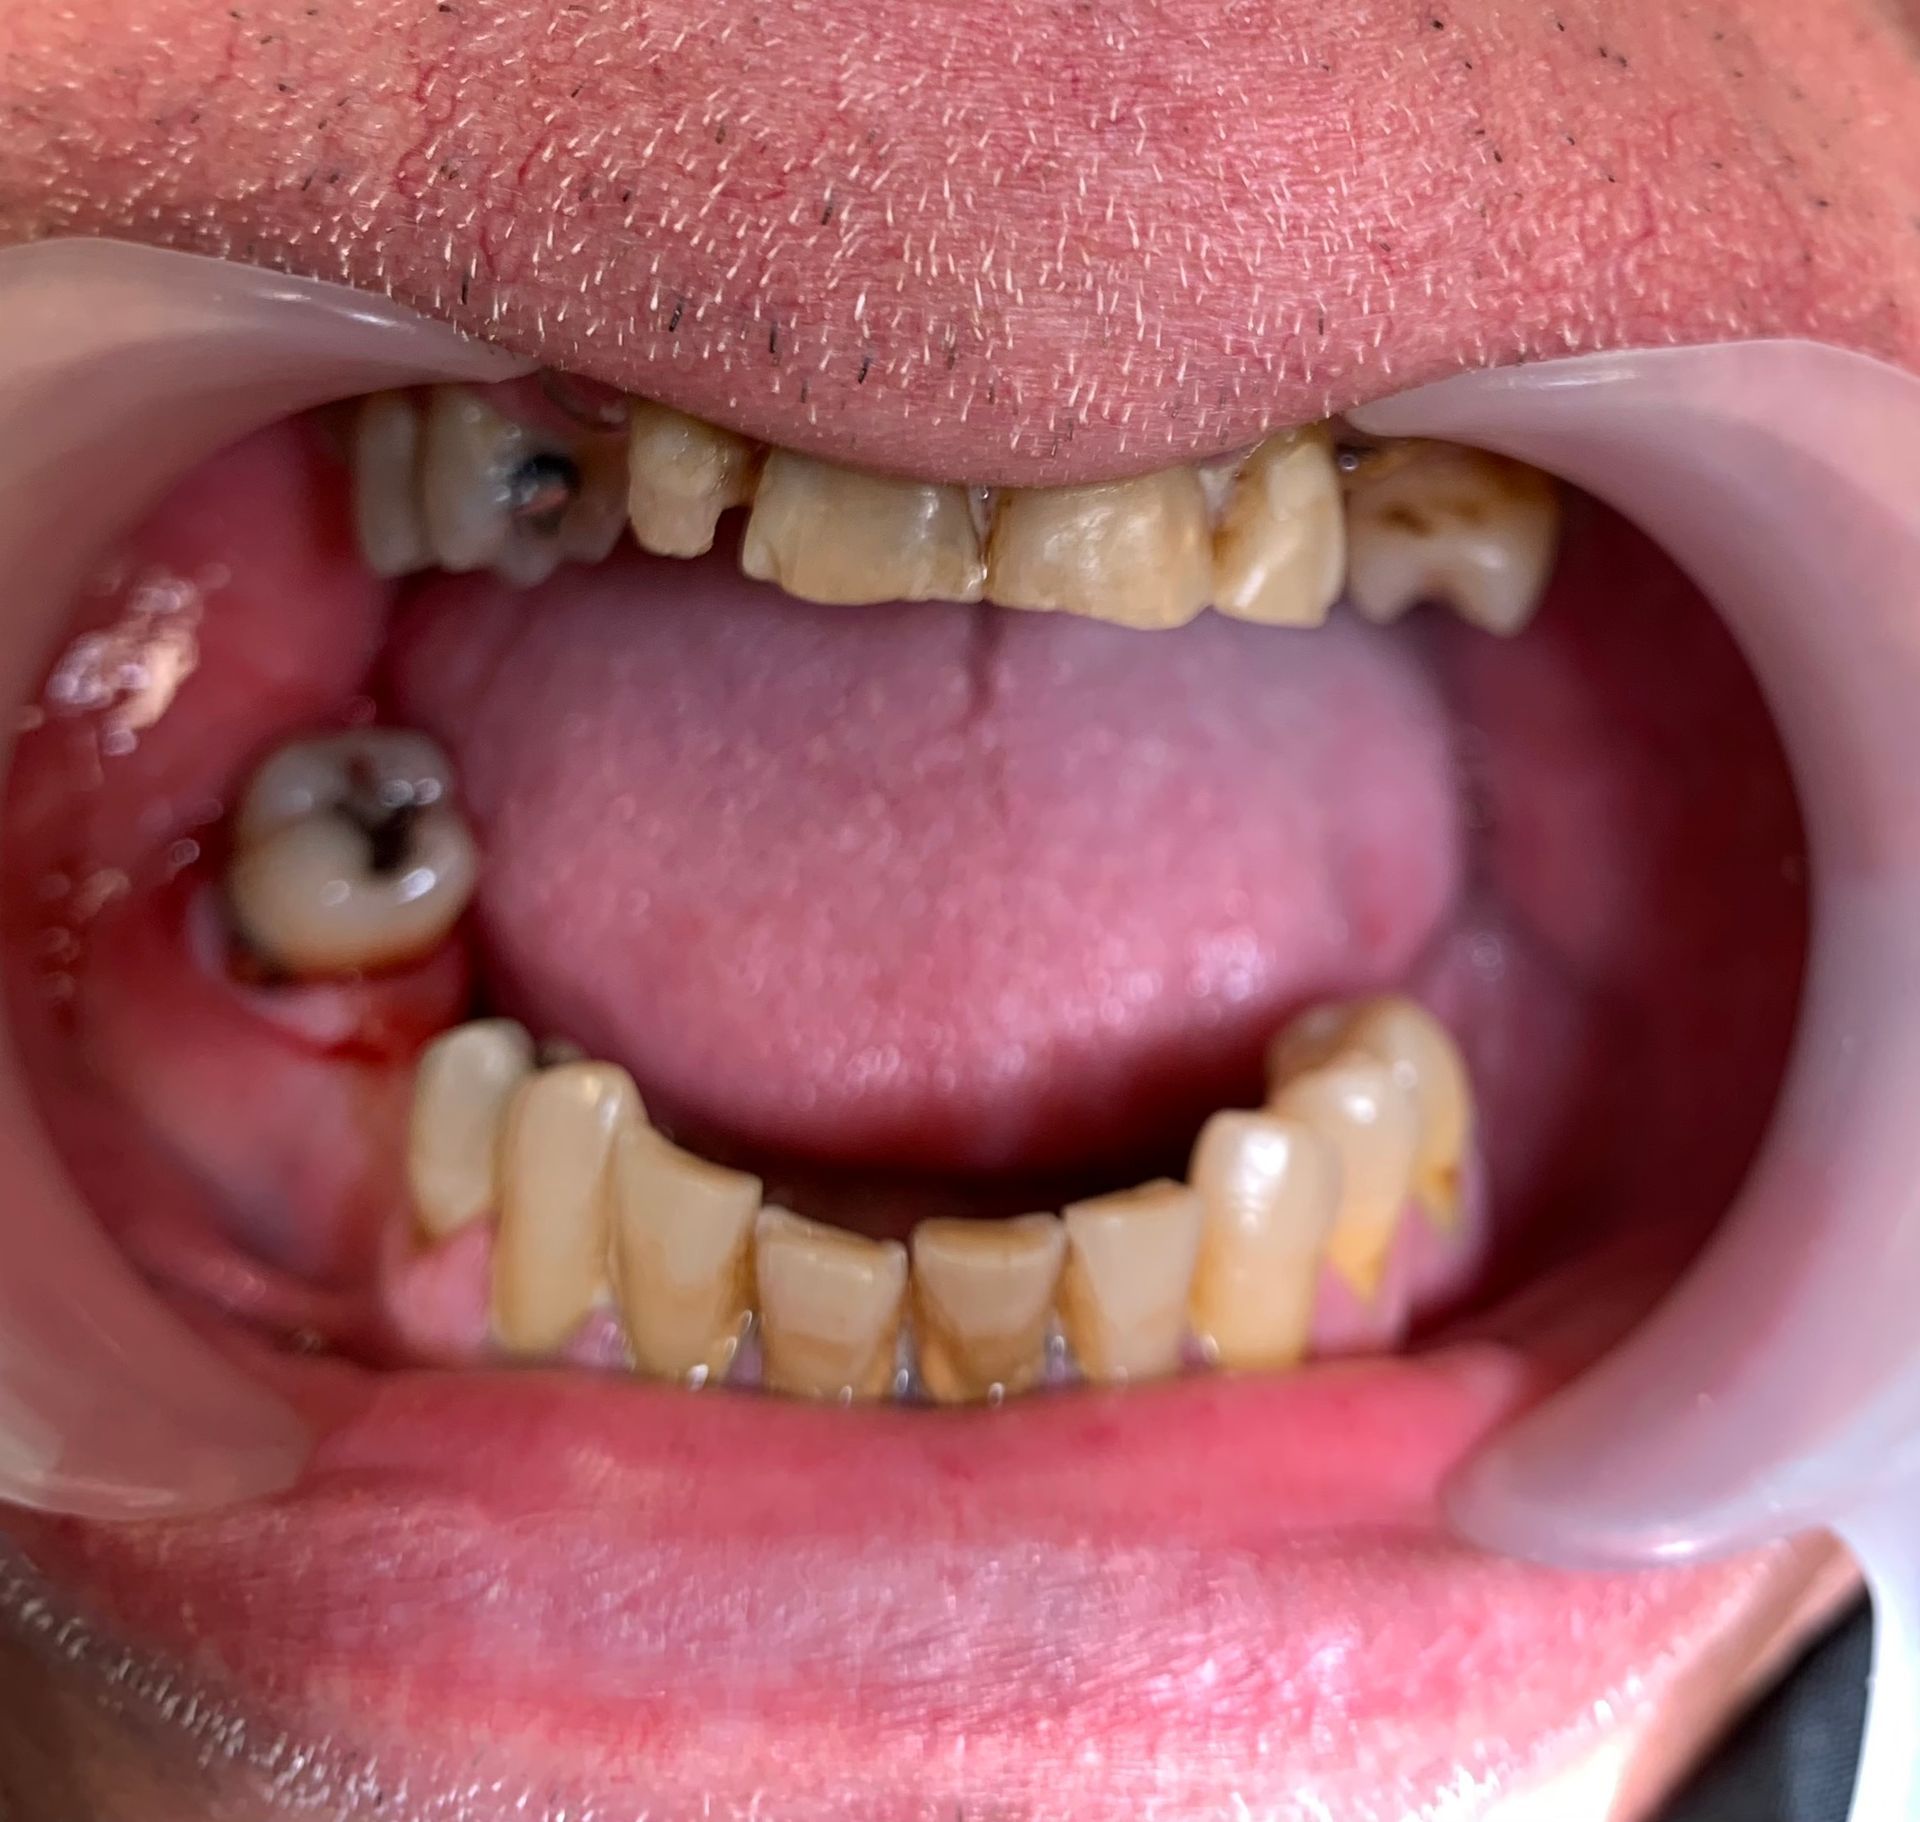

CASO NUMERO 2: UN'EMERGENZA DENTALE SUI DENTI SUPERIORI

Una paziente si presenta alla nostra osservazione dopo un

grave trauma funzionale ed estetico dopo un incidente stradale...

ButtonUna paziente si presenta alla nostra osservazione dopo un grave trauma funzionale ed estetetico per un incidente stradale.